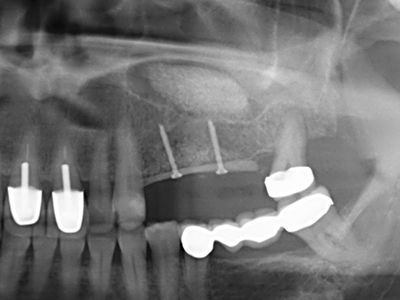

Abb. 24: Anbringen des Distraktors (TRACK-System, KLS Martin).

Abb. 25: OPTG nach Erreichen der finalen Distraktionshöhe, vor Konsolidierungsperiode.

Abb. 26: Nach einer Konsolidierungs-phase von vier Monaten zeigen sich stabile Verhältnisse vor Implantatinsertion.

Wie sich in der Vergangenheit gezeigt hat stellt prinzipiell jeder knochenchirurgische Eingriff eine mögliche Indikation für die Piezochirurgie dar. So lässt sich die Präparation des mobilen Segmentes bei der Distraktionsosteogenese (Abb. 23-25) und der Sandwichosteotomie mit speziellen Ansätzen bewerkstelligen, ohne die für den Erfolg beider Techniken essenzielle Blutversorgung des krestalen Anteils zu gefährden (Gonzalez-Garcia, Diniz-Freitas et al. 2008).

Abb. 21: Ausgedehnter OK-Frontzahndefekt mit Indikation zur Distraktionsosteogenese bei vernarbtem Weichgewebe nach Vor-Operation.

Abb. 22: Das mobile Segment kann präzise mit der dünnen Osteotomiesäge (W&H Piezomed) separiert werden.

Abb. 23: Finale Mobilisation des palatinal gestielten Distraktionssegmentes mit dem Meissel.